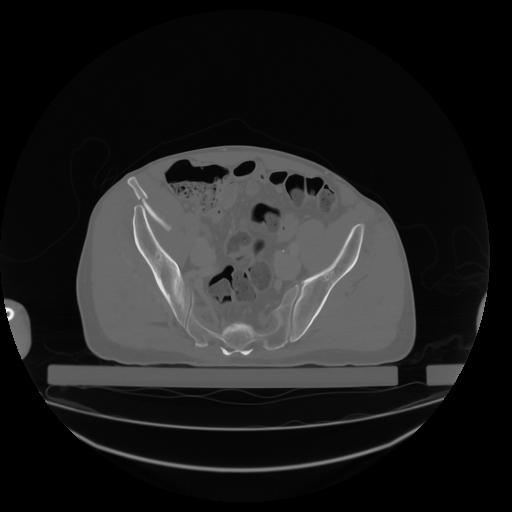

27 CUERPO,CE,Axial,3.0,CUERPO,,